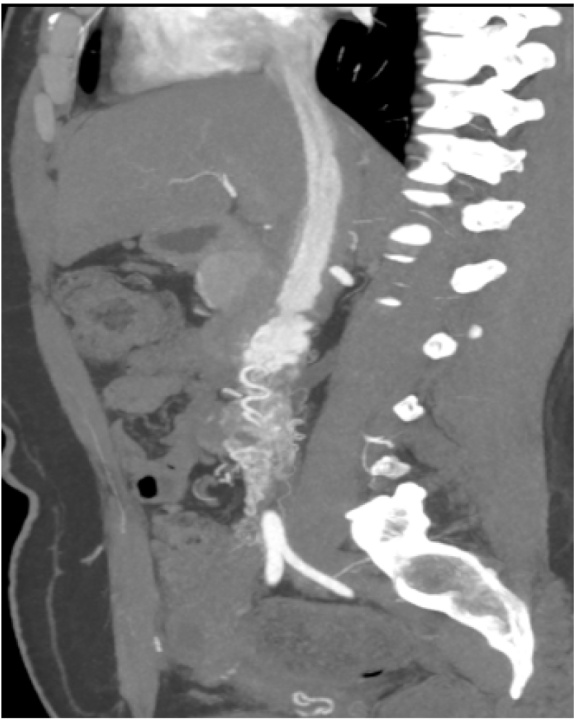

(a) 为VR后面观 (b) 冠状位MPR图像 (c) 斜矢状位MPR图像

(d) VR图像 (e) 斜矢状位MIP图像 (f) 斜冠状位MPR图像

(a)、(b),一例Ⅱ期子宫静脉内平滑肌瘤病,VR重建后面观图像及冠状位MPR图像清晰显示子宫右侧区域存在边界不清的强化肿块,该病灶呈现特征性蠕虫样形态,沿右侧卵巢静脉走行并最终汇入下腔静脉;值得注意的是,下腔静脉腔内可见异常强化血管影,形成典型的“血管内血管”征象。(c)、(d) 另一例Ⅱ期病例显示,斜矢状位MPR图像和VR重建图像中可见子宫右侧肿块内存在多发结节状、蠕虫状及条索状显著强化病灶,这些病灶沿右侧髂内静脉延伸至下腔静脉,同时下腔静脉内再次观察到具有诊断价值的“血管内血管”征。(e)、(f),在Ⅲ期病例的影像表现中,斜矢状位MIP图像与斜冠状位MPR图像共同证实病变已进展至右心房区域,并呈现特征性的“拐杖头”形态。

Figure 1. Stage Ⅱ and Ⅲ uterine intravenous leiomyomatosis (IVL)

1. Ⅱ、Ⅲ期子宫静脉内平滑肌瘤病